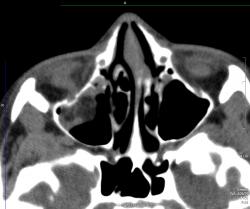

Отломок напоминает открытую дверцу, в которую вываливается нижняя прямая мышца и клетчатка. Бывает, что такая "дверца" захлопывается и ущемляет содержимое орбиты. Тут нужен зоркий глаз и знание клиники, так как сам перелом можно уже и не увидеть, отломок встал на место.

Зрение в порядке за исключением "пустяка" диплопии. Почему называется взрывным переломом? Вероятно потому, что перелом не от прямого удара по кости, иначе ломался бы край орибы. Ломается тонкое место в дне орбиты от резко повышения давления в орбите в результате прямого удара. Американцы приводят как пример типичный механизм прямого удара бейсбольным мячом. Как ни странно, медиальная стенка ломается реже, и еще реже верхняя стенка.

У меня тоже два случая подряд прошли недавно. Оба - нижняя стенка. В одном случае - с гемосинусом, в другом - без. На рутинных рентгенограммах переломчики не видны, но если учитывая клинику присмотреться, то мы увидим мягкотканную тень ущемленной клетчатки свисающей в гайморовую пазуху. Взрывной перелом получается, если предмет, ударивший по глазу, больше по размерам диаметра орбиты. У нас в одном случае -коленка соседа, в другом - кулак)))